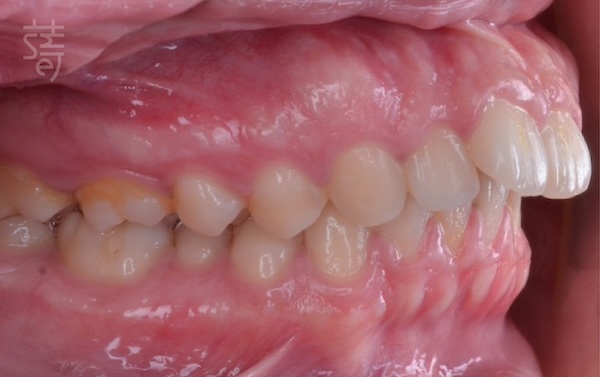

初診時,我們為鄭老師安排了完整的隱適美評估,透過X光檢查與口腔掃描,發現她有明顯的上顎前突與下巴偏小的問題,這不僅影響外觀比例,還影響到咬合功能與整體口腔健康。

為讓矯正效果更理想,我們建議她搭配拔牙與正顎手術,創造足夠的排列空間,同時改善咬合關係。這樣的治療計劃對她來說並不輕鬆,但在充分討論與耐心說明後,她鼓起勇氣,選擇相信我們,也相信自己能一步步走完這段路。